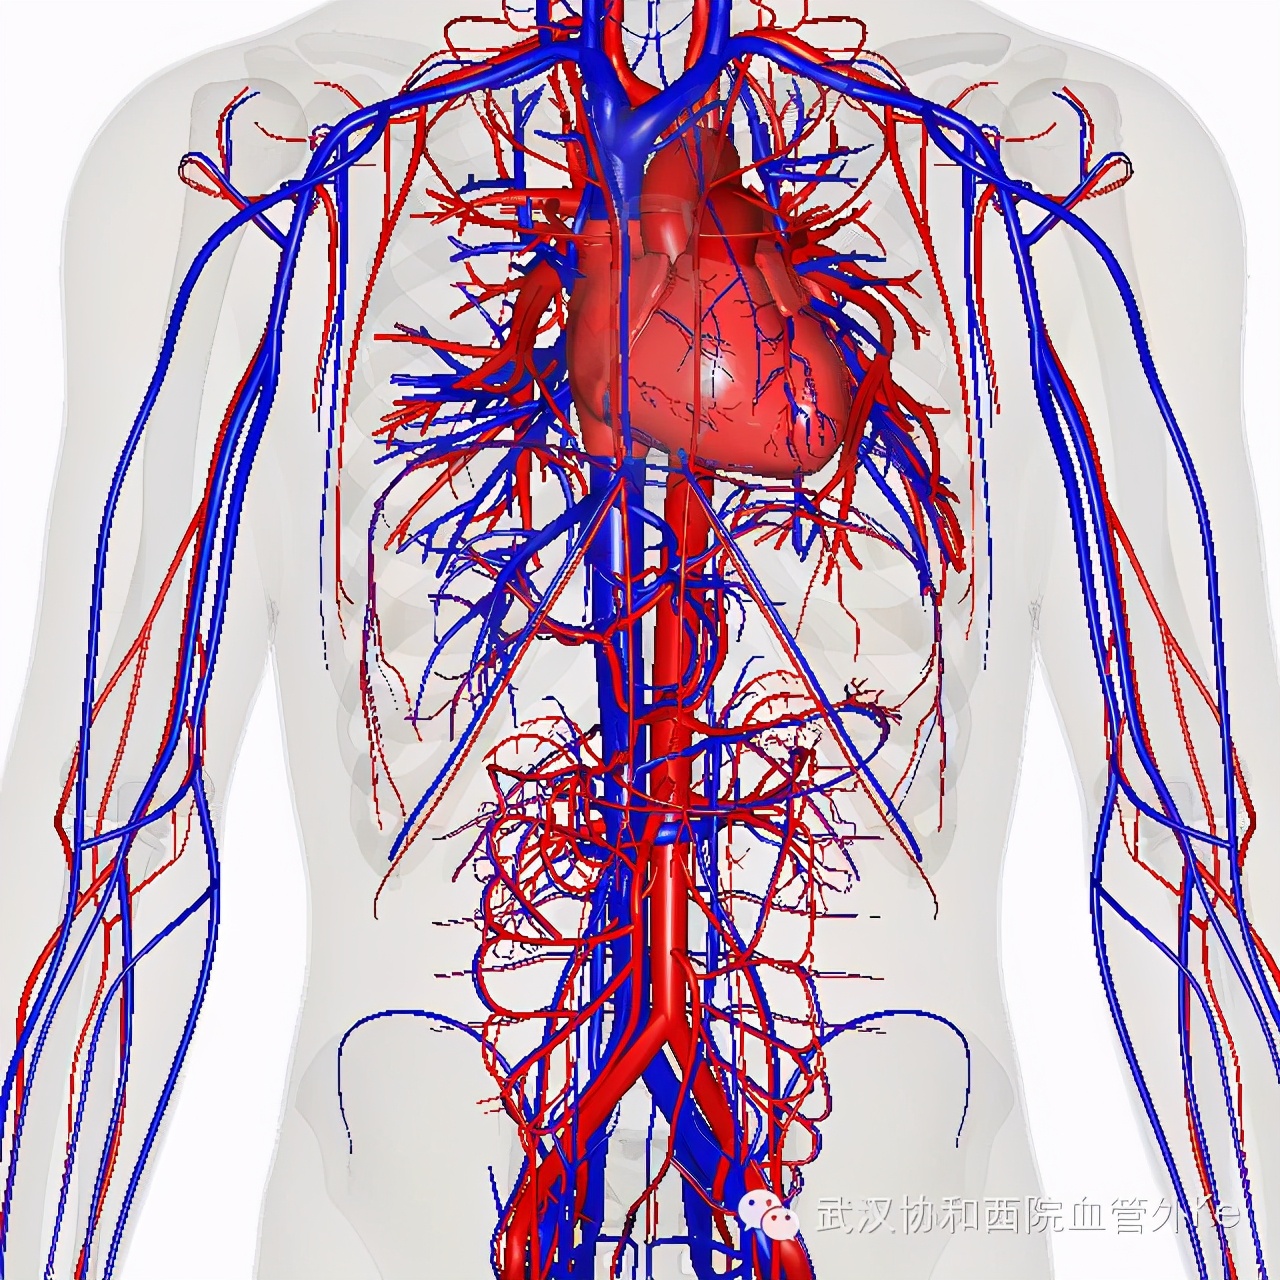

严格意义上,血管外科应该称之为 peripheral vascular surgery(周围血管外科)。它是负责全身除心脏以外循环系统各处血管发生的疾病,如动脉硬化狭窄闭塞,动脉瘤或夹层等动脉扩张疾病,静脉血栓,静脉曲张以及各种血管畸形,还包括可通过血管介入手段治疗的疾病等。如果您出现了以下这些症状,建议及时到血管外科就诊排查是否存在血管疾病。